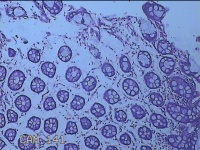

乙状结肠粘膜

性别

男

年龄

52岁

临床诊断

结肠息肉

一般病史

乙状结肠可见息肉

标本名称

大体所见

灰白粉红色组织小米大一团。

图4

自动采图系统很方便,图片采太多没病变的图,几张就够了,而且制片技术急需改进,

有点增生性息肉的感觉